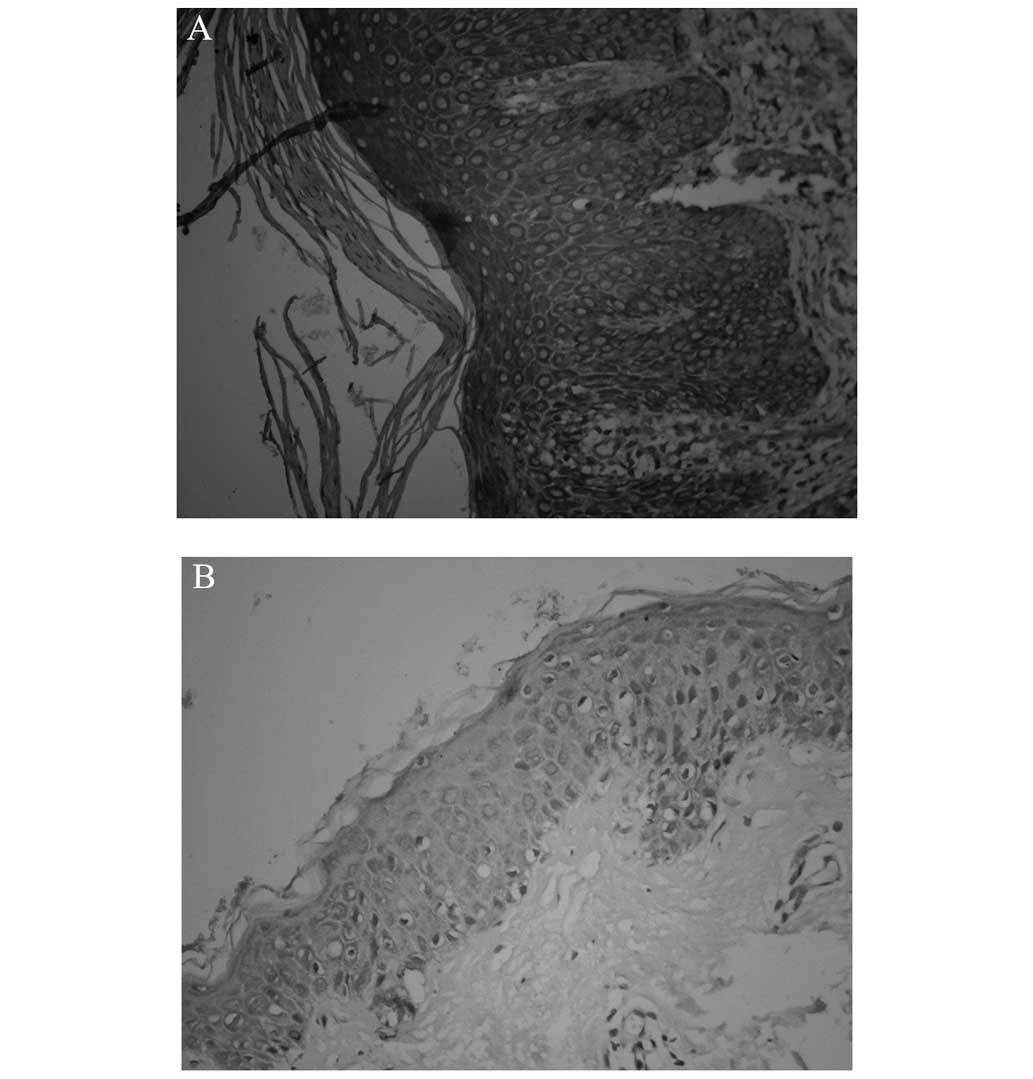

In healthy skin, RIP4 was found predominantly in the basal layer of the epidermis; by contrast, the expression in the psoriatic lesions was concentrated in the basal and spinous layers, in the cytoplasm and nuclei of the cells. Analysis of the OD showed the mean OD (MOD) of RIP4 in the healthy controls to be 0.11±0.03, compared with 0.30±0.05 in the psoriasis vulgaris lesions. This revealed a statistically significant upregulation in the psoriatic lesions (t=7.71, P<0.01) (Figs. 1 and 2).

In the healthy control skin, Ki-67-positive cells only appeared sporadically in the basal layer. By contrast, Ki-67-positive cells in the psoriatic specimens were distributed in not only the basal layer but also the middle and lower parts of the rete ridges of the lesional epidermis. The proliferation index of the psoriatic lesions was 20.01±7.90%, while that of the healthy control skin was 10.67±4.92%; this suggested that the Ki-67 expression in the psoriatic lesions was significantly higher than that in the healthy control skin (t=4.535, P<0.05) (Fig 3). In addition, Pearson's correlation analysis demonstrated a significantly positive correlation between the RIP4 MOD and the proliferation index, which indicated that a high level of RIP4 expression led to the active proliferation of keratinocytes in the epidermis (r=0.692, P<0.01) (Fig. 4).